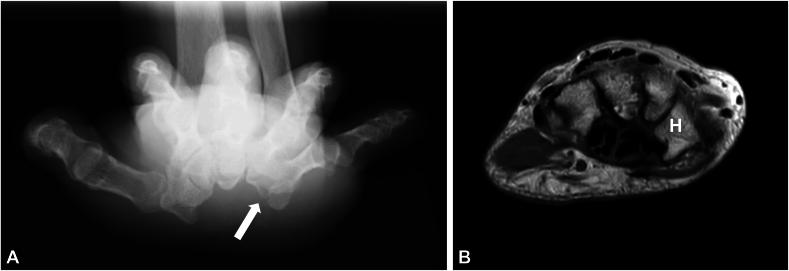

This retrospective study included 65 hands of 57 patients (8 men and 49 women; mean age, 64.9 years) who underwent endoscopic carpal tunnel release for carpal tunnel syndrome at our hospital between March 2016 and April 2022. The patients were diagnosed with carpal tunnel syndrome based on clinical observations and electrophysiological studies. On T2-weighted magnetic resonance axial images, the height of the hook of the hamate was measured from the bottom to the tip of the hook, and the total height of the hamate was measured from the dorsal surface of the hamate to the tip of the hook. A hook-to-height ratio of less than 0.34 was defined as hypoplastic, and its incidence was investigated. In addition, electrodiagnostic testing of sensory and motor nerve conduction of the median nerve and patient-reported outcome measurements, including Quick Disabilities of the Arm, Shoulder and Hand score, Boston carpal tunnel questionnaire, and visual analog scale score, were investigated at 6 months after surgery. Adverse events were collected from patient records.

The mean hook-to-height ratio was 0.40. Hypoplasia with a ratio ≤0.34 was observed in seven hands (10.8%), and adverse events were observed only in the two cases that had a hypoplastic hook of the hamate (3.07%). The patient-reported outcome measurements and the result of electrodiagnostic testing at 6 months after surgery did not correlate with the height of the hook of the hamate.

这项回顾性研究纳入了2016年3月至2022年4月期间在我院因腕管综合征接受内镜下腕管松解术的57例患者(8例男性和49例女性;平均年龄64.9岁)的65只手。患者根据临床观察和电生理研究被诊断为腕管综合征。在T2加权磁共振轴向图像上,从钩骨钩的底部到钩尖测量钩骨钩的高度,从钩骨的背侧表面到钩尖测量钩骨的总高度。钩高比小于0.34被定义为发育不全,并对其发生率进行调查。此外,在术后6个月对正中神经的感觉和运动神经传导进行电诊断测试,并对患者报告的结局指标进行测量,包括手臂、肩部和手部快速残疾评分、波士顿腕管问卷和视觉模拟量表评分。从患者记录中收集不良事件。

平均钩高比为0.40。7只手(10.8%)观察到钩高比≤0.3四的发育不全,仅在2例钩骨钩发育不全的病例中观察到不良事件(3.07%)。术后6个月患者报告的结局指标测量和电诊断测试结果与钩骨钩的高度无关。